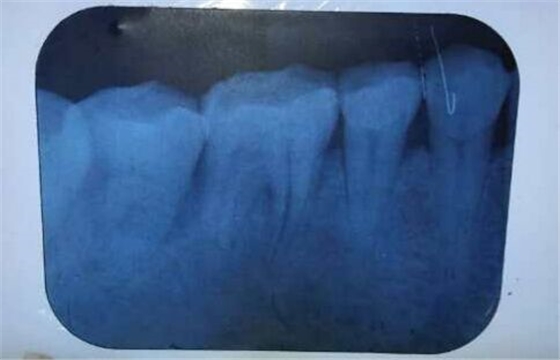

根管隱裂病例

來(lái)源于江思玉2群收集整理